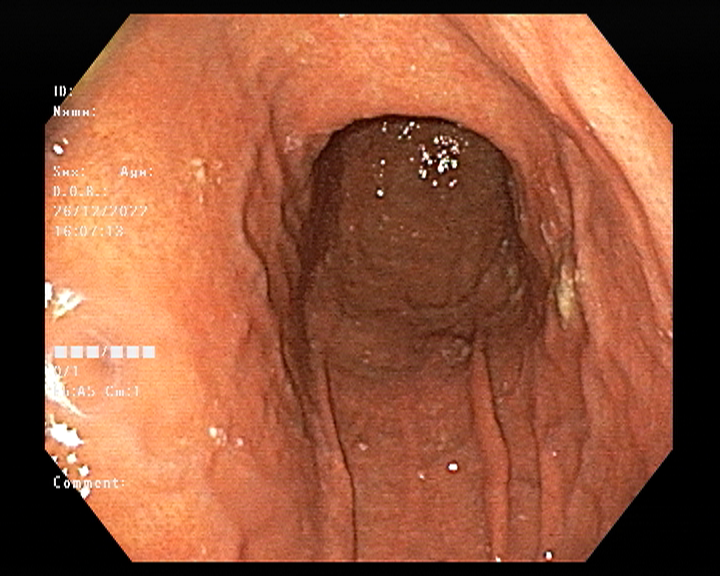

Endoscopy and colonoscopy are safe and accurate procedures used to directly examine the digestive tract and detect the root cause of chronic acidity, GERD, abdominal pain, bleeding, and bowel irregularities. These minimally invasive tests help identify ulcers, inflammation, infections, polyps, strictures, and early cancerous changes.

At Sapphire Gastroenterology Center, modern endoscopic equipment ensures precise diagnosis and, when required, therapeutic intervention during the same procedure. Based on findings, targeted treatment plans are created, including medication, diet guidance, and preventive strategies. Early diagnosis through endoscopy and colonoscopy plays a crucial role in preventing serious complications and improving long-term digestive health.